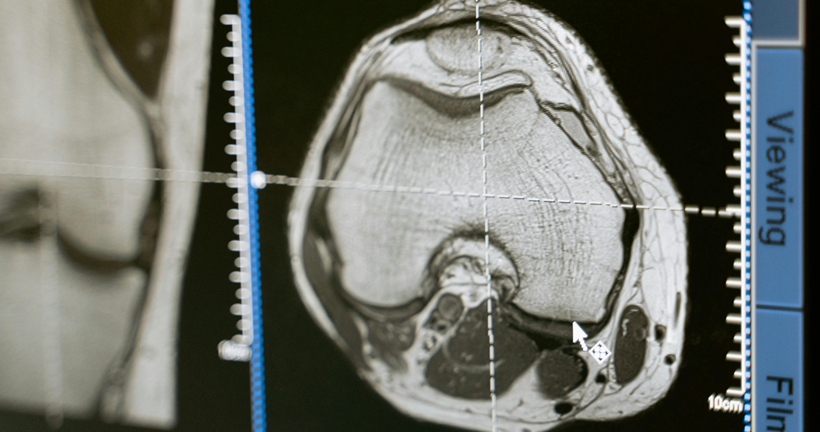

La presentación sintomatológica de la disfunción frontal dependerá de si la afectación predominante inmiscuye a regiones del cíngulo u orbitales. Además, las afectaciones de las funciones ejecutivas dependerán del daño en la corteza dorsolateral. Buscamos describir la relación existente entre la atrofia cerebral identificada en estudios de resonancia magnética estructural, PET-FDG y su implicación cognitiva sobre los pacientes con DFTvnf.

Como resultados en relación con los estudios analizados, se encontró que solo el 15% de artículos mantienen una correlación de áreas anatómicas - cognitivas, además se encontraron alteraciones en los dominios de atención, memoria y funciones ejecutivas mientras que los hallazgos de atrofia cerebral se localizan en áreas frontales, el cíngulo e ínsula.

El diagnóstico de la DFTvnf es un proceso complejo que se compone de distintas etapas, por lo que, la presente revisión sistemática confirma la importancia de estudio de las manifestaciones clínicas, la evaluación neuropsicológica de procesos cognitivos y el papel de las técnicas de neuroimagen en la identificación de este tipo de variantes.